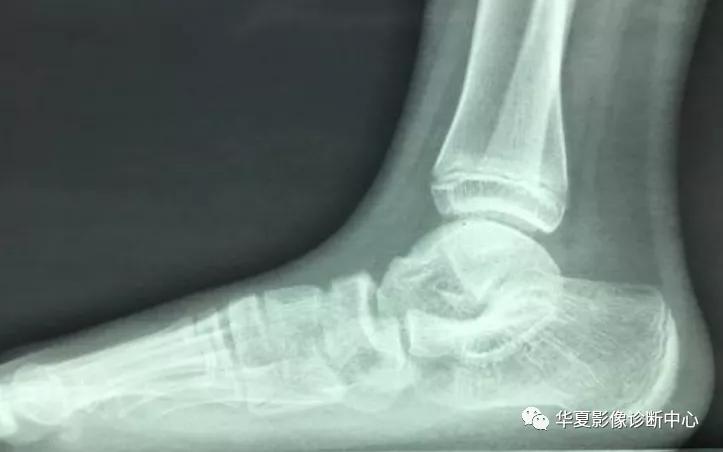

放射学检查:拍摄足负重正侧位 ,45°内斜位,跟骨轴位X线片。

二、跟距融合:好发年龄为12-16岁,扁平足腓侧面痛性强直,休息后可缓解,最常见的发病部位是过距突中部的平面,X线表现为距骨颈或距骨头的背面凸起的距骨嘴损伤(66%),围绕距骨的侧面,跟距关节后方变窄,中间面缺乏分界,跟距关节前方不对称,严重者可出现“袜套球”踝关节,侧位片距骨中间顶呈C形改变,后下方距骨圆穹与支撑部形成骨桥。CT表现为跟距关节中间面骨性连接,变窄的中间面可见反应性小囊状变及肥大增生改变,支撑部呈向下或水平。